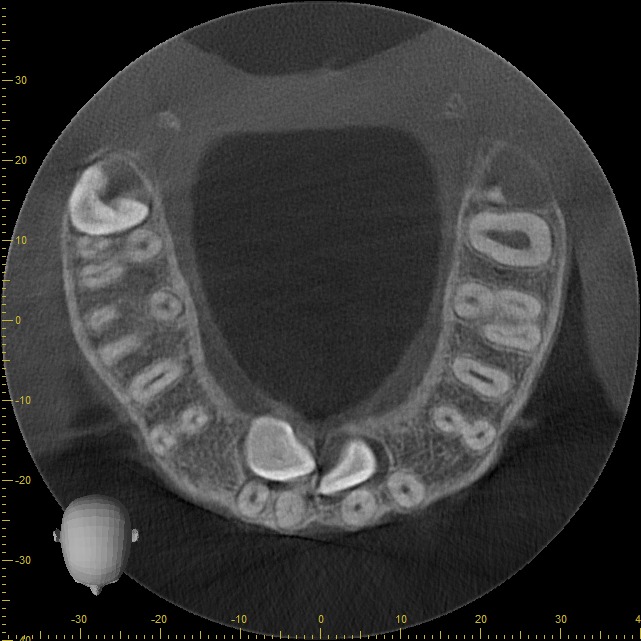

• Rápido – Cómodo – Eficaz: Las imágenes obtenidas con nuestros equipos son altamente detalladas, mostrando los tejidos duros sin perder calidad.

Podemos analizar la posición y orientación de estructuras críticas como los nervios, las raíces dentales, los senos paranasales y la nariz, lo que ayuda a lograr un diagnóstico lo más preciso posible. Con nuestra tecnología de imagen avanzada, tu odontólogo podrá monitorear la estabilidad a largo plazo de tus restauraciones dentales, de esta forma se podrá obtener el resultado estético que deseas con tu tratamiento.